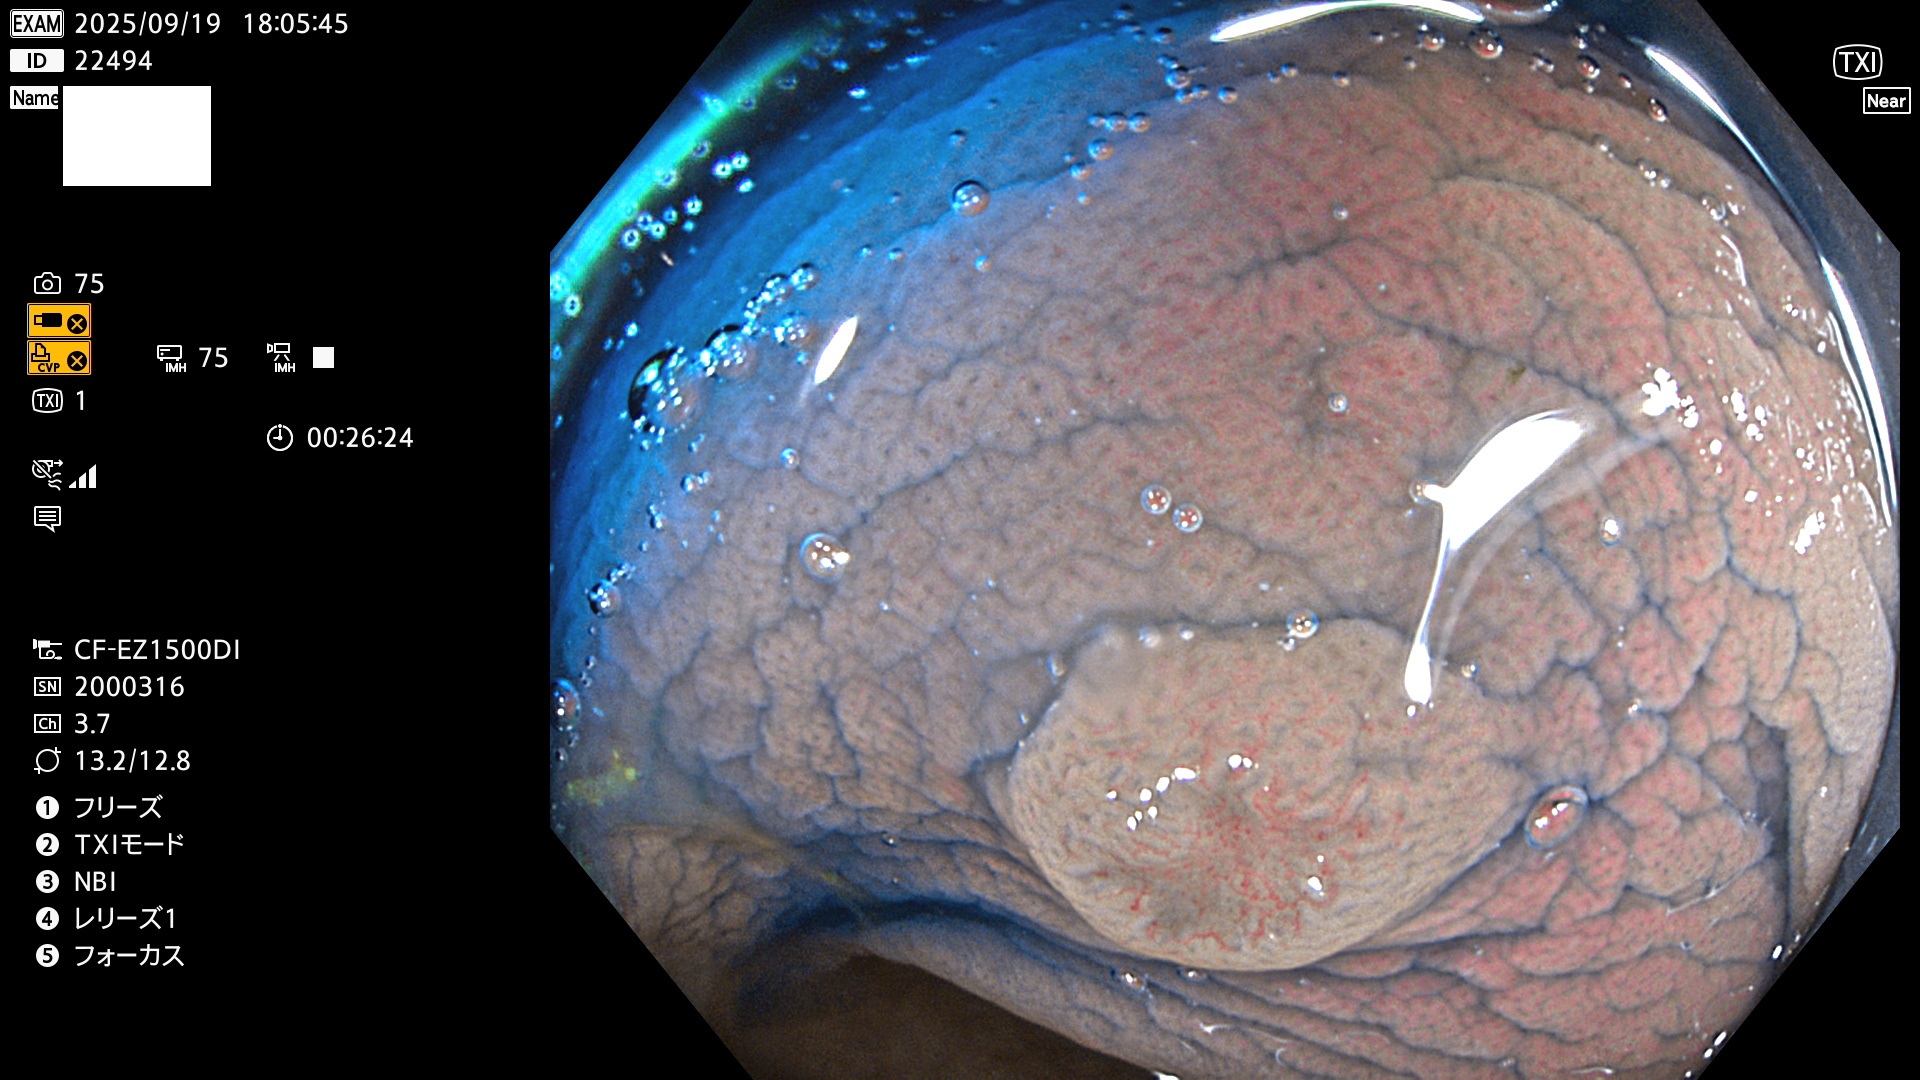

完全に平坦な物をUb、陥凹している物をUcと呼びます。Ubは認識が困難で、Ucはびらん(炎症)と紛らわしいために見落とされやすく、「内視鏡後・大腸癌」の原因になります。

専門的)何故、陥凹していると危険? 癌遺伝子の変異が蓄積すると細胞分裂が盛んになり隆起するのでは?と通常は思われるでしょう。しかし実際は逆です。これは2022年の記事にある「細胞はストレスに直面したら細胞分裂を止める(Dormancy 細胞老化に入り休眠する)という生命の基本的現象」によるものです(Oncogene Stress)。細胞老化を起こすのが癌抑制遺伝子で、この安全装置(ブレーキ)が壊れると癌になります(休眠からの覚醒)。ですから陥凹は「まだ癌では無いが癌化の直前」を意味します。特に「小サイズなのに陥凹している」病変は短期間に腫瘍進化(IntraTumor Heterogenity⇒2021年記事)が起きたことを意味します(=ゲノム不安定性)。

専門的)細胞生物学的Ucの再定義UcをPitと形態学で定義するのは医学的には全く不毛です。Ucの本質はIntraTumor HeterogenityとTumor Dormancyが微小病変に見られる点です。これは早い腫瘍進化=ゲノム不安定性を意味します。そのような病変は隆起型でも形態によらずUcと定義すべきです。なぜなら1年後には陥凹し典型的Uc(最悪の場合NPG癌)になるからです。

毎週の検査(木・金・土・日)に発見されたUbとUc型・腺腫を、その週の日曜の夜にUPし1週間、提示します。

2025年9月17日〜9月21日の4日間(40件)6個 (Uc_ADR=6個/40人=15%)